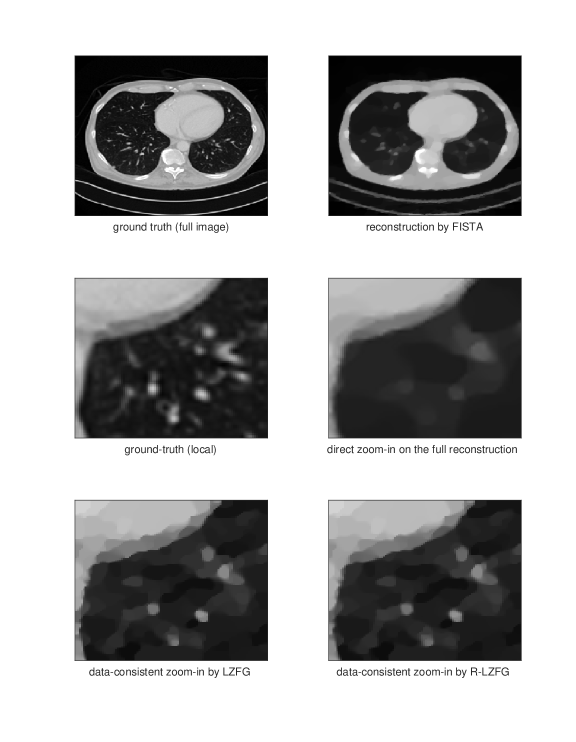

and we take the logarithm for the linearization of the measurements. We choose a low measurement energy with and the forward operator for low-dose CT example; while and for sparse-view CT example. We run all the experiments here in MATLAB R2020b. Given the measurement and full operator, we solve a TV-regularized least-squares optimization problem by FISTA and get a global estimate of the ground truth. As we can observe, the reconstructed images have a reasonable global quality but could oversmooth some of the local areas which may need to be refined and zoomed in. In this example, we seek to zoom-in 4 times larger a by block of a by image. Hence, the global iterative superresolution of the whole image will be at least 25 times more computationally expensive than our approach in this setting. Direct zoom-in on this block would often have poor performance since it does not re-utilize the measurement data. We then test our LZFG and R-LZFG, both using TV-regularization. We use the MATLAB imresize function as the up-sampling and down-sampling operators, with the default bicubic interpolation.

In Figures 2 and 3 we present two examples of local zoom-in. We can observe from the numerical results that our method can indeed recover the details of the local blocks in high quality. The direct zoom-in from the first-stage reconstruction fails to recover local details missed from the first-stage reconstruction since it does not utilize the measurement data, demonstrating the importance of data consistency in local zoom-in of medical images. We present the convergence curves of LZFG and R-LZFG in Figure 1 reporting the PSNR results towards the zoomed-in ground-truth image. From the PSNR result, we can observe that our methods provide significantly improved reconstruction accuracy (around 2 to 5 dB better) compared to the direct approach, which does not take into account the measurement data. Meanwhile, we also observe that the R-LZFG with adaptive restart can further improve the convergence performance in the final stage of the LZFG as shown in Figure 1, leading to a slight increase in PSNR within our computational budget.